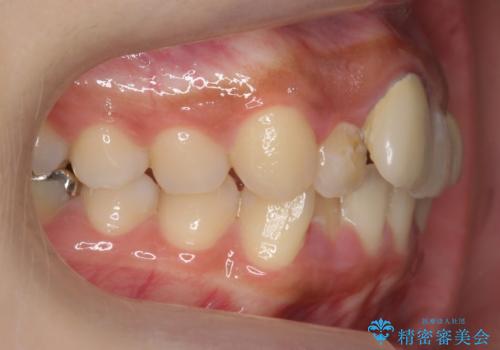

前歯のがたつき 保険治療の前歯の被せ物もやりかえたい

- 前歯のがたつきを主訴に来院。

保険治療の被せ物が前歯に2本あり、矯正治療で移動後にセラミックでやり替えを行っています。

右上のかみ合わせがずれていたため、インプラント矯正を行い、奥歯を後ろに下げて治療しています。